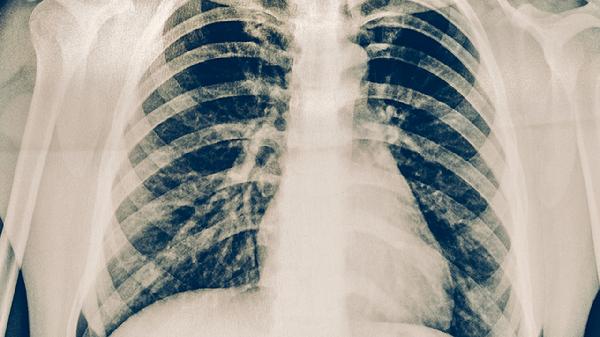

肺结核的治疗是一个长期、规范的过程,患者必须严格遵循医嘱,完成足量、足疗程的联合化疗,切忌自行停药或更改剂量,否则极易导致治疗失败或产生耐药。在药物治疗期间,应保证充足的营养支持,多摄入富含优质蛋白和维生素的食物,如鸡蛋、牛奶、瘦肉、新鲜蔬菜水果等,以增强机体修复能力。保持居住环境通风,注意休息,避免劳累和情绪波动,进行适度的康复锻炼。定期复查胸部影像学和痰菌检查至关重要,以便医生评估疗效和调整方案。若出现恶心、皮疹、黄疸、视力异常等不适,应及时与医生沟通。